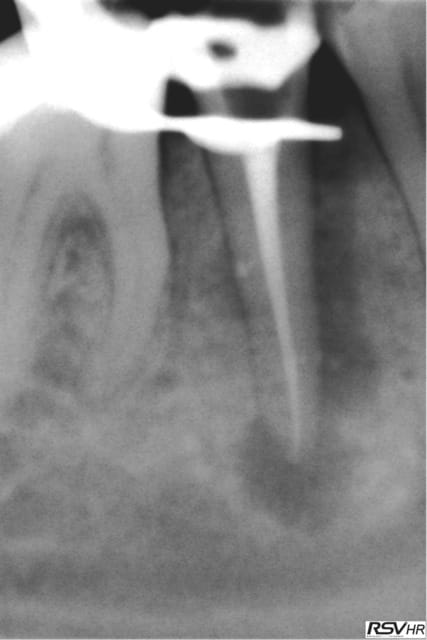

je joins un cas de traitement sur 45 ;nécrobiose,digue,hypo

1 instrument acier en cathétérisme,séquence NITI héroshaper

20%à6% puis4% 25à4% 30à4%,sealite regular,1 cône gutta fine-médium,1 compactage avec thermocompacteur(traitement

sous A.B car risques de douleurs par reprise bactérienne

Chances: des canaux secondaires obturés par le ciment

guérison de l'apex pas de douleurs pendant le compactage

cône de gutta avec "tug back" légère sensation d'échauffement

pas de douleurs post-opératoires

Un rêve....(sauf pas de HN;reconstitution SC33;sauvé par la CCM)!